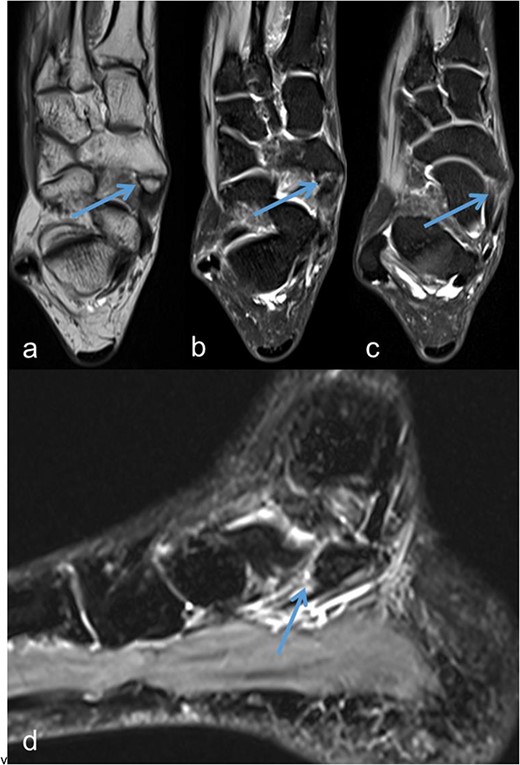

A 53-year-old man with a body mass index of 22.3 kg/m2 reported severe, load-dependent pain (6 out of 10 on the VAS) in the left foot, which had increased over the past two months. Light jogging as a recreational sport was no longer possible due to pain, and no trauma was recalled. Clinically, there was a mild pes planovalgus, with slight swelling and warmth medioplantarly and distal to the medial malleolus along the course of the tibialis posterior tendon. A marked point tenderness was noted, and forced dorsiflexion was severely painful. Conventional radiographs showed a triangular Type II Os tibiale externum at the typical site, measuring approximately 10.5 x 6 mm (Fig. 1a and b). Additional CT imaging in the axial plane with coronal reconstruction and subsequent 3D reconstruction (Fig. 2a and b) revealed a Type II Os tibiale externum with a distinct synchondrosis gap to the navicular bone. An MRI showed central inflammatory reaction in the synchondrosis and significant perifocal soft tissue edema of the Os tibiale externum with involvement of the tibialis posterior tendon, with no tendon rupture detected (Fig. 3a–d).

Os tibiale externum Type II in the coronal T1-weighted MRI scan (a), inflammatory reaction/tendinosis at the insertion of the tendon of the tibialis posterior muscle visualized in the heavily T2-weighted, fat-suppressed MRI scans (b and c), synchondrosis between the Os tibiale externum Type II and Os naviculare with central and perifocal edema visualized in the sagittal heavily T2-weighted, fat-suppressed MRI scan (d); each marked with an arrow.